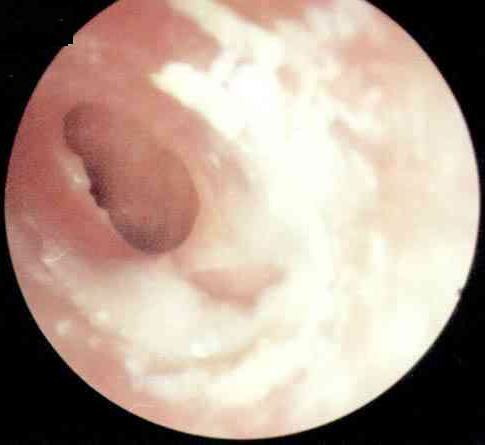

中耳炎病理图

西安新城中大耳鼻喉医院 张全安教授介绍,对于耳朵流脓,许多人都认为没什么了不起,是小毛病。但事实上,由于人的耳部与头颅内的脑膜很接近,中耳若感染发炎,可以通过血液循环或是通过内耳直接扩展到颅内,而引起颅内的并发症,严重时可以危及患者的生命安全。经过检查发现,刘先生属于化脓性中耳炎,病灶已侵犯到脑部造成脑脓肿从而导致头部剧烈疼痛,这个时候如果脓肿破裂则随时有生命危险。随后冯亮医生根据他的病情量身制定了诊疗方案,终于除掉了隐患。